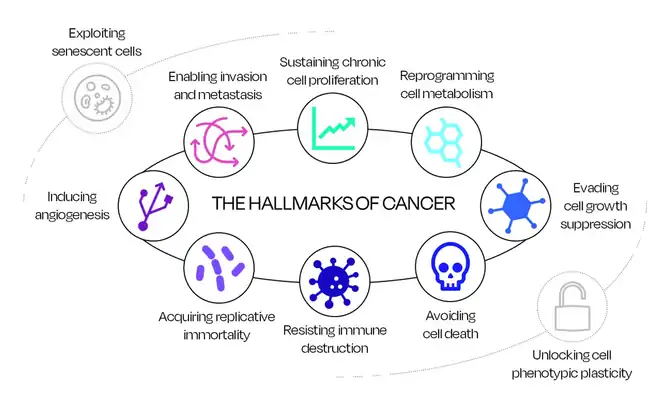

Marqueurs du cancer

Le cancer est un organe complexe[16]. Les tumeurs sont des agrégats de plusieurs types de cellules interagissant avec l’ensemble de l’organisme via leur microenvironnement. Un paradigme de longue date consiste à considérer le cancer comme une maladie uniquement génétique, étant donné la complexité des modifications génétiques associées à la tumorigenèse. Cependant, les tumeurs se comportent comme un système beaucoup plus complexe, incorporant une variété de cellules non dérivées de tumeurs, et pas seulement des cellules tumorales génétiquement modifiées[16]. Certaines caractéristiques de l'oncogenèse ressemblent à des processus de développement d'organes et de remodelage tissulaire ; en particulier le microenvironnement tumoral, qui subit des changements environnants favorables à la croissance et à la prolifération cellulaires[17]. Les technologies capables d’exploiter toutes les caractéristiques de l’interaction complexe entre les cellules cancéreuses et l’ensemble du corps, localement et systémiquement, y compris les réponses mutationnelles, métaboliques et immunitaires, pourraient être essentielles à la détection précoce du cancer.

Les caractéristiques du cancer peuvent être définis comme les principes qui forment ensemble un cadre organisé de caractéristiques significatives aptes à décrire les mécanismes et les processus contribuant à la formation néoplasique à la fois au niveau génétique et métabolique[18],[19]. Néanmoins, l’interaction du système immunitaire dans la formation du cancer est considérée comme une caractéristique émergente, jouant un rôle important dans la promotion d’un état inflammatoire qui peut encourager, mais aussi inhiber, la formation de néoplasie[18],[20]. Les mécanismes qui se produisent dans le corps humain autour du microenvironnement tumoral ne sont pas encore entièrement compris, ce qui présente de nombreux défis dans la quête d'une détection précoce et de thérapies efficaces[21],[22],[23].

Maintenir une prolifération cellulaire chronique

L’attribut cardinal du cancer consiste à entretenir une prolifération chronique de cellules tumorales. Les signaux d'activation sont généralement transmis par des ligands de facteurs de croissance se liant aux récepteurs de la surface cellulaire, via des voies de signalisation intracellulaires, qui régulent le cycle cellulaire et le développement, la survie et le métabolisme cellulaire. Malgré la nature complexe de ces signaux dans les tissus normaux et cancéreux, le mécanisme de signalisation proliférative dans le microenvironnement tumoral a été étudié et compris de manière approfondie[18] ; les cellules cancéreuses peuvent auto-produire des ligands de facteurs de croissance ou stimuler les cellules normales pour recevoir des apports en facteurs de croissance[24],[25],[26],[27].

Reprogrammer le métabolisme cellulaire

Des ajustements du métabolisme énergétique sont nécessaires pour maintenir la prolifération incontrôlée des cellules tumorales, car les cellules doivent être alimentées en énergie pour subir des cycles de croissance et de division. Les cellules normales subissent une glycolyse dans des conditions aérobies pour produire un rendement élevé en adénosine triphosphate (énergie métabolique) ; dans des conditions anaérobies, la glycolyse peut toujours se produire, mais le rendement énergétique est plus faible. Les cellules tumorales utilisent systématiquement la glycolyse anaérobie, ce qui entraîne une absorption constante de glucose pour compenser la production réduite d'adénosine triphosphate ; cette caractéristique du métabolisme des cellules cancéreuses prend le nom d’« effet Warburg »[18],[28]. D’autres cellules tumorales utilisent le lactate (c’est-à-dire un sous-produit de la glycolyse anaérobie) comme principale source d’énergie, créant ainsi un système symbiotique fonctionnant parfaitement[29]. Outre le glucose et le lactate, les acides aminés ont également été récemment revendiqués comme d'importantes sources de carburant opportunistes pour le développement du cancer ; la glutamine et les acides aminés à chaîne ramifiée contribuent spécifiquement au soutien du cycle acide citrique (ou cycle de l'acide tricarboxylique)[30].

Éviter l'arrêt de la croissance cellulaire

Les gènes suppresseurs de tumeurs codent généralement pour la protéine du rétinoblastome et la protéine tumorale 53 (TP53), qui contrôlent à la fois la prolifération cellulaire et l'activation de la sénescence (c'est-à-dire l'état de dormance) et de l'apoptose (c'est-à-dire la mort cellulaire)[18] . La protéine du rétinoblastome est un gardien du cycle cellulaire et des défauts dans la protéine peuvent entraîner une prolifération persistante[31]. De la même manière, la protéine P53 contribue aux circuits de régulation en arrêtant la progression du cycle cellulaire lorsque les capteurs de stress/anomalies signalent un niveau élevé de dommages génomiques ; sa carence peut permettre à la cellule cancéreuse de progresser dans sa croissance[18] . De plus, la corruption de la voie du facteur de croissance transformant antiprolifératif β contribue à la croissance cellulaire et est considérée comme étant la clé du développement de traits cellulaires de haut grade associés à une malignité[18],[32].

Éviter la mort cellulaire

Les dommages génomiques arrêtent le cycle cellulaire pour réparer la séquence altérée ou envoyer des signaux d’activation de la mort cellulaire lorsque les dommages sont trop importants. Certaines cellules cancéreuses peuvent résister à cette barrière naturelle, évitant ainsi la mort cellulaire programmée par apoptose. Cependant, toutes les cellules ne sont pas immunisées contre l’apoptose ; de nombreuses cellules cancéreuses subissent encore la mort cellulaire en raison du stress physiologique provoqué par la tumorigenèse et/ou le traitement anticancéreux[18]. Les cytochromes c, la protéine Bax et la protéine Bak sont les protéines régulatrices de la famille Bcl-2 chargées de contrebalancer les signaux pro et anti-apoptotiques ; des dommages à la transcription de ces protéines entraîneront des déséquilibres dans les processus de régulation des cellules[33]. L'autophagie et la nécroptose sont également déclenchées par un stress/des dommages génomiques[34],[35],[36].

Résister à la destruction par le système immunitaire

Toutes les cellules immunitaires ne favorisent pas les tumeurs, la plupart des cellules du système immunitaire sont capables de défendre l’organisme contre les agents pathogènes, et les cellules cancéreuses sont souvent considérées comme l’une d’entre elles, activant la cascade immunitaire[18]. Initialement présentée comme une caractéristique émergente, la capacité des cellules cancéreuses à éviter activement l'élimination du système immunitaire a été confirmée par Hanahan, et de nombreuses expériences ont été menées pour étudier cette caractéristique[18],[37]. L'importance du système immunitaire dans la lutte contre la formation et la prolifération du cancer a été étudiée en comparant des sujets immunodéprimés et des porteurs de greffe, montrant comment les cancers se forment plus facilement dans des environnements immunogènes faibles[38],[39],[40].

Acquérir l'immortalité

La capacité des cellules cancéreuses à acquérir une immortalité réplicative peut être décrite comme la capacité de subir un nombre suffisant de cycles cellulaires successifs de croissance et de division pour générer des tumeurs macroscopiques[18]. Les télomères, qui sont des structures ADN-protéines spécifiques situées aux extrémités des chromosomes et qui protègent leur séquence génomique de divers événements de réplication négative, sont cruciaux pour cette caractéristique[41]. Leur longueur dicte la quantité de cycles de croissance et de division qu'une cellule peut supporter, c'est pourquoi l'immortalité réplicative est rendue possible par des cellules variantes qui maintiennent l'ADN télomérique à des longueurs suffisantes pour éviter le déclencheur de sénescence/apoptose[18].

Induire la formation de nouveau vaisseau

Au cours de la croissance néoplasique, de nouveaux vaisseaux sanguins germent à partir de ceux existants (c'est-à-dire l'angiogenèse) pour faciliter l'expansion de la tumeur, constituant un interrupteur angiogénique établi qui semble être activé et maintenu uniquement pendant la tumorigenèse[42]. Il existe une variété de facteurs considérés comme proangiogéniques et contribuant à l’activation du commutateur angiogénique. Un inducteur angiogénique bien connu est le gène du facteur de croissance de l’endothélium vasculaire (VEGF-A), qui code pour des ligands aptes à la croissance de nouveaux vaisseaux à plusieurs étapes de la progression individuelle et du maintien de la santé, depuis la promotion du développement embryonnaire jusqu’aux situations pathologiques de l'adulte[18]. La signalisation oncogène régule positivement l'expression du gène VEGF[43].

Permettre l’évasion des cellules et la formation de métastase

Une fois la tumeur primitive formée, le processus en plusieurs étapes d'invasion et de métastases se produit. La combinaison des processus qui conduisent à l'invasion des cellules tumorales et à la formation et à la colonisation de métastases est complexe, il existe donc de nombreuses hypothèses. concernant leur fonctionnement et leur importance[18]. Il a été démontré que certains cancers peuvent métastaser à des stades précoces de la maladie ; les micro-métastases peuvent se disperser à partir de tumeurs de nature non invasive et la faible capacité à retenir les cellules cancéreuses dans leur système sanguin/lymphatique entraîne une invasion plus facile du parenchyme[44],[45].

Débloquer la plasticité phénotypique cellulaire

La plasticité phénotypique fait référence à la capacité des cellules à modifier leur réponse comportementale en fonction des impulsions environnementales. La plasticité cellulaire est généralement bien construite et les cellules suivent un chemin préfixé depuis la cellule d'origine jusqu'à une cellule terminale différenciée, dans laquelle une cellule change pour se spécialiser dans une fonction spécifique. La capacité d'un état cancéreux à débloquer cette plasticité phénotypique entraîne une différenciation cellulaire dérégulée où elles échappent à la différenciation prédéterminée[37],[46]. Les altérations de la voie de différenciation sont retrouvées dans divers types de cancer au cours de la formation de la tumeur primaire, de l'évolution vers une tumeur maligne et, dans certains cas, en réponse à des traitements thérapeutiques[37].

Exploiter la sénescence

La capacité des cellules cancéreuses à échapper au stade de sénescence et à permettre l'immortalité réplicative a été décrit par Hanahan et[18]. Le composants du phénotype sécrétoire associé à la sénescence (Senescence-associated secretory phenotype) comprennent des facteurs de croissance et pro-inflammatoires, tels que les cytokines, parmi une variété d'enzymes et de protéines[47]. Le composant du phénotype sécrétoire associé à la sénescence est responsable des cellules sénescentes sécrétant des niveaux plus élevés de facteurs favorisant la croissance, qui déclenchent la formation de néoplasie en donnant accès également à d'autres caractéristiques importantes du cancer comme une prolifération cellulaire continue, une immortalité, une accélération de l'angiogenèse et la formation de métastases[37],[48],[49].